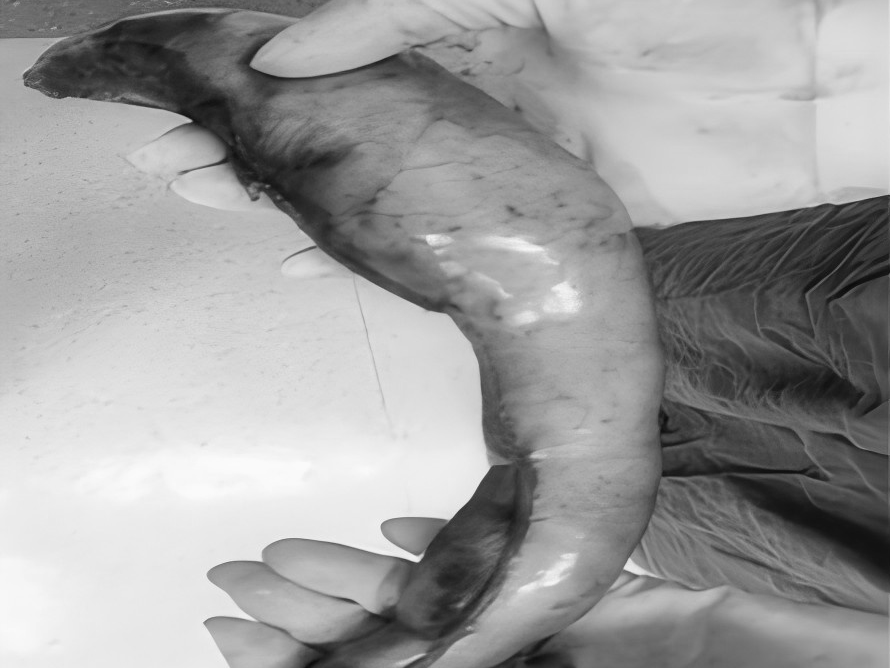

诊室里,经常能看到这样的画面:家长抱着哭得小脸通红、怎么哄都停不下来的宝宝,急急忙忙冲进来,“医生!快看看!孩子大腿根这里突然鼓了个包,越来越大!这可怎么办啊?!”——这种让人揪心的紧急情况,很多都是“小儿疝气”(俗称“小肠气”)惹的祸! 什么是小儿疝气? 简单说,就是宝宝肚子上有个“小洞洞”没长好(发病率为1%-4%),医学名称叫“腹股沟疝”,是小宝宝(尤其是男宝)很常见的一种情况。 为啥会这样?宝宝在妈妈肚子里时(先天性),腹股沟那里有个通道(学名叫“鞘状突”)本该自己关上的,但没关严实,就成了个“小洞洞”。当宝宝使劲哭闹、咳嗽、或者用力便便时,肚子里压力一大,一小段肠子或者组织就可能从这个“小洞洞”钻出,鼓起一个“包”。 最典型的表现:宝宝大腿根附近,出现一个“鼓包”,而且这个包在宝宝安静或躺平时,常常能自己缩回去(或者家长轻轻一推就能推回去)。 家长最关心的问题 1.必须要做手术吗? 在1岁以内有长好的可能,可以观察看看。超过1岁还没好,或者包块反复卡住(嵌顿)引起剧痛,千万别等了,尽早做手术,最佳手术年龄通常是1到3岁。 2.麻醉会不会伤脑子? 手术用的是全身麻醉,目前全球尚无研究证实规范全麻操作会影响智力或记忆力。宝宝就像睡了一个很沉很沉的觉,手术过程中完全没感觉、也不会记得。 为什么腹腔镜修补术比较适合宝宝? 传统开刀手术需在大腿根附近切开一个3厘米左右长的口子,手术后会留下挺明显的疤,恢复也慢。 腹腔镜修补术是通过肚子上3-5毫米(米粒般的大小)的小孔进行手术,同时能探查并处理对侧“隐性疝”,一次手术就搞定,不用再挨第二刀。术后一般6-8小时可以下床,24小时后能出院。 术前术后,家长这样配合更安心 术前准备 1.手术前6到8个小时别让孩子吃东西、喝水,防止打麻药时吐出来呛到。 2.按医生要求做抽血、凝血这些检查,看看孩子身体适不适合手术。 3.手术前一天给孩子洗个澡,把肚脐和大腿根附近洗干净。 4.多哄哄孩子,别让他哭得太厉害(哭狠了肚子里压力大,对手术不好)。 术后护理 饮食:术后6小时可少量喂水,无呕吐可逐渐恢复正常饮食。 活动:术后一周避免剧烈跑跳、哭闹或用力排便,防止腹压过高。 伤口护理:保持伤口清洁干燥,若发现红肿、渗液等不适,及时联系医生。 注:部分图片来源于网络,如有侵权,请联系删除。 贵州航天医院普外科专家简介 高大勇 普外科(肛肠外科)学科带头人、名誉主任,主任医师、教授 临床擅长:对中西医结合诊治肛肠学科各种常见病、多发病及疑难杂症等具有丰富的临床经验。 原遵义市第一人民医院(遵义医科大学第三附属医院)、遵义市中医院肛肠科主任。中华中医药学会肛肠分会常委,全国中医肛肠学科名专家,中国健康促进与教育协会肛肠分会常委,中国康复医学会肛肠疾病康复专业委员会常委,中国民间中医医药研究开发协会肛肠分会副秘书长,中国医师协会中西医结合肛肠医师专业委员会常委,国家二级心理咨询师,贵州省第一批中医名医工作指导老师,遵义市名中医,遵义市肛肠学会会长,遵义市肛肠质控中心名誉主任,遵义市中西医结合学会名誉会长,遵义市健康科普专家,原贵州省中西医结合学会肛肠分会副主任委员、贵州省中医肛肠质控中心副主任、遵义市医学会医疗鉴定委员会专家、遵义市卫生系列高评委。发表论文30余篇,主编和参编医学著作5本,主持省级科研课题2项、市级科研课题2项、院级科研课题1项。 梁 跃 中共党员,普外科党支部书记、主任,主任医师 临床擅长:对普外科各类肿瘤手术具有丰富的临床经验。 毕业于遵义医学院,遵义市医学会小儿外科学分会常务委员,遵义市肛肠协会理事,遵义市医学会核医学分会(第二届)委员会委员;荣获第三期“黔医人才计划”优秀学员称号;主持市级课题1项,完成省级课题1项,在国内各类刊物上发表论文10余篇。 钱科洪 民盟盟员,普外科副主任医师 临床擅长:从事普外科临床工作30余年,对各类普外科疾病的诊治、乳腺、甲状腺、胃十二指肠、结直肠等疾病及疑难杂症具有丰富的临床经验。 毕业于遵义医学院临床医疗系,2009年前往中山大学附属第一医院微创外科进修学习,在国内各专业期刊发表论文数篇。 贵州航天医院普外科简介 基本情况 贵州航天医院普外科成立于1968年,前身属于航天部O61基地3417医院外一科,1998年3417医院、3427医院合并后更名为普外科,下设胃肠外科、肛肠外科2个亚专业科室,拥有在全市较为先进的专科设备和技术,是中国疝病专科联盟单位,贵州医科大学附属医院胃肠外科专科联盟单位。开放床位40张,配备医护人员21人。 专科特色 普外科致力于胃肠及肛肠疾病的外科临床诊治及科研,以腹腔镜微创外科技术为本,形成以快速康复治疗胃肿瘤、结直肠肿瘤、小肠肿瘤、直肠脱垂、肥胖病、急腹症、各类疝、痔、瘘等专科特色,同时注重胃肠疾病尤其是结直肠恶性肿瘤的基础研究和临床转化研究,总体诊断和治疗水平在区域同级医院居于领先水平。 开展手术:腹腔镜下胃癌根治术,腹腔镜下袖状胃切除术,腹腔镜下胃肠道间质瘤切除术,腹腔镜下结、直肠癌根治术,胃癌、结直肠癌的精准治疗,腹腔镜下小儿疝气、成人疝修补术,腹腔镜下阑尾手术,内痔的硬化注射治疗及痔疮的微创治疗:ATH、PPH、TST,直肠脱垂的各种手术治疗,难治性伤口VSD技术,鼻胃肠管、肠梗阻导管置入术,肛肠术后间歇性导尿技术,并引进了中医适宜技术,也为各种化疗患者提供输液港安装,提高患者就医体验。 腹腔镜下腹股沟疝 无张力修补术 腹股沟疝里金斯坦(Lichtenstein)手术 PPH微创术治疗环状混合痔 黏连性或炎性肠梗阻-肠梗阻导管 腹腔镜袖状胃切除 腹腔镜阑尾切除术 腹腔镜阑尾肿瘤切除术 腹腔镜下结肠癌根治术 诊疗范围 胃肿瘤、结直肠肿瘤、小肠肿瘤、肥胖症、各类急腹症、腹部外伤、腹壁疝、便秘、直肠脱垂、痔疮、肛瘘、肛裂等胃肠、肛肠外科疾病。 END